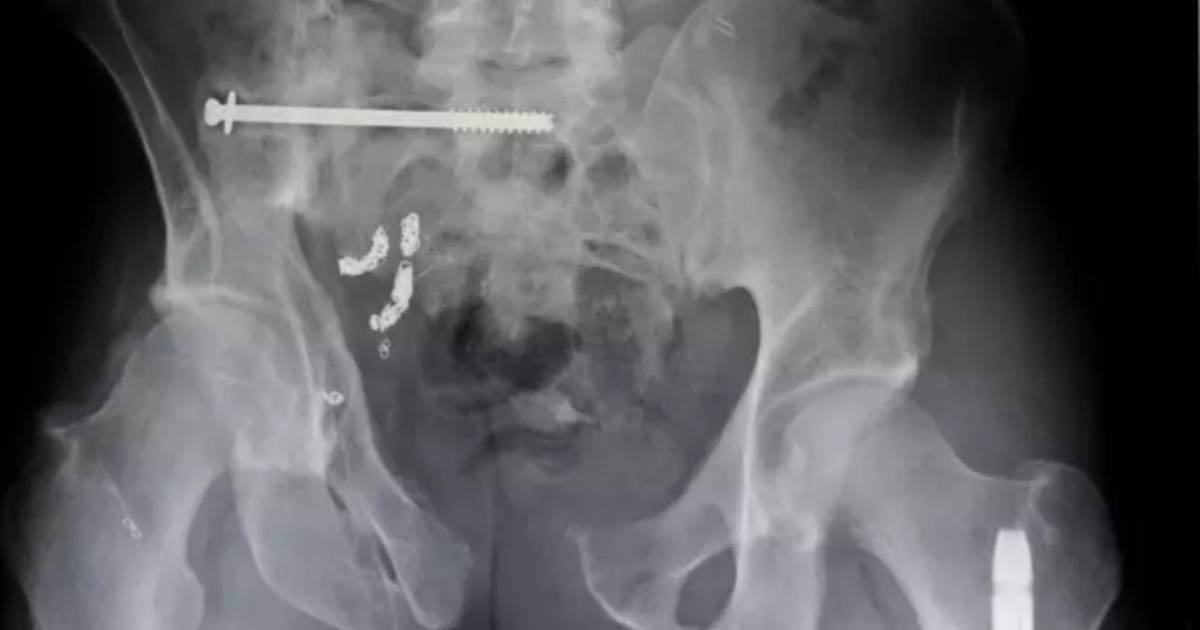

- Βίδες και καρφιά